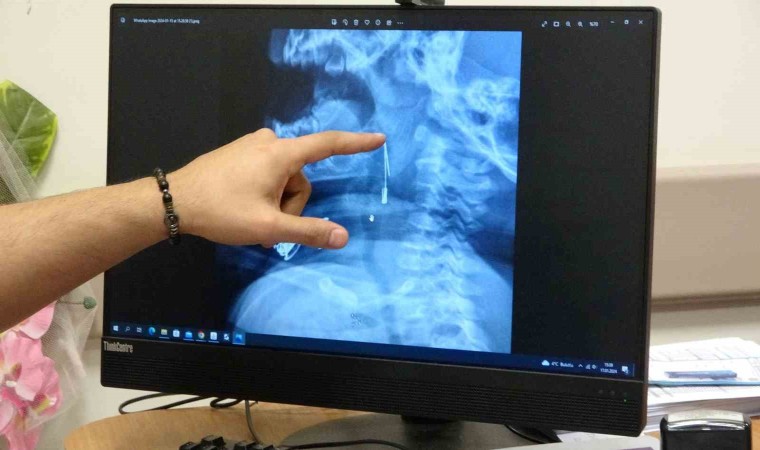

Güroymak ilçesinde 8 aylık bebek, evde bulunan çengelli iğneyle oynarken onu yuttu. Öksürmeye başlayan minik çocuğun, hastanede çekilen röntgen sonucu çengelli iğneyi yuttuğu fark edildi. Güroymak Devlet Hastanesi’nden Tatvan Devlet Hastanesi’ne ambulansla sevki gerçekleşen minik çocuk, Kulak Burun Boğaz Hastalıkları Uzmanı Operatör Dr. Hakan Tuhan tarafından yapılan başarılı operasyonla sağlığına kavuştu. Çengelli iğnenin saplı olduğu soluk borusundan çıkarılan bebek, 2 saatlik gözlemin ardından taburcu edildi.

Konuyla ilgili açıklamada bulunan Kulak Burun Boğaz Hastalıkları Uzmanı Operatör Dr. Hakan Tuhan, “8 aylık bir bebek, Bitlis’in Güroymak ilçesinden tarafımıza danışıldı. Güroymak ilçesinde çekilen röntgen sonucunda çengelli iğnenin soluk borusunun girişinde olduğunu teyit ettik. Yapılan müdahaleler sonucunda çengelli iğneyi çıkardık. Çıkardıktan sonra iki saat kadar gözlem altında tuttuk hastamızı. Daha sonrasında herhangi bir komplikasyonla karşılaşmadık ve sorunsuz bir şekilde taburcu ettik” dedi.